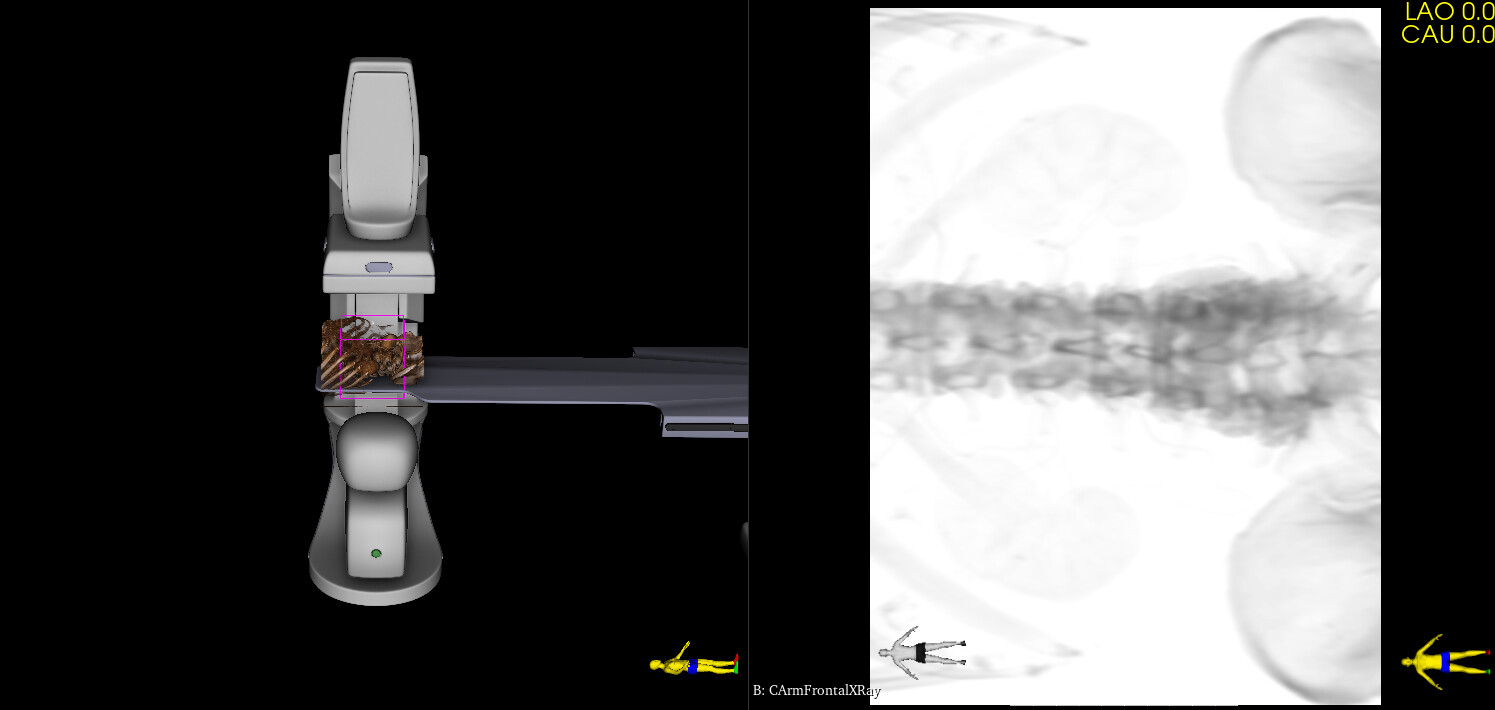

I’ve updated the module with the followings:

• Added detector rotation angle (no auto-rotation is available, but the rotation can be easily manually adjusted on the GUI)

• Default L arm angle is set the C-arm to be at the side of the table

• Projection beam is displayed (to make it easier to see the field of view in 3D)

• Detector size is configurable in the preset .csv files

Nice image! You show the vessel in the simulated fluoro image as a surface rendering now. You can try to use the “Virtual contrast filling” section to make the appearance more realistic (the module fills the CT image uniformly inside the segment/model with the density you specify).

Virtual contrast filling can be useful to simulate stronger contrast filling (e.g., you have a CT with IV contrast injection and you want to simulate local contrast injection) or you want to add anything to the CT that was originally not there (e.g., a stent or device).

Here is the procedural image with the C-arm oriented as simulated. I find it a faithful reproduction for a first try, and remain confident for subsequent ones.

Here it means less radio emission and less contrast medium injection.

This module should be viewed as a wonderful add-on to anyone working with a C-arm, beyond the cardio-vascular realm, orthopedists for example.